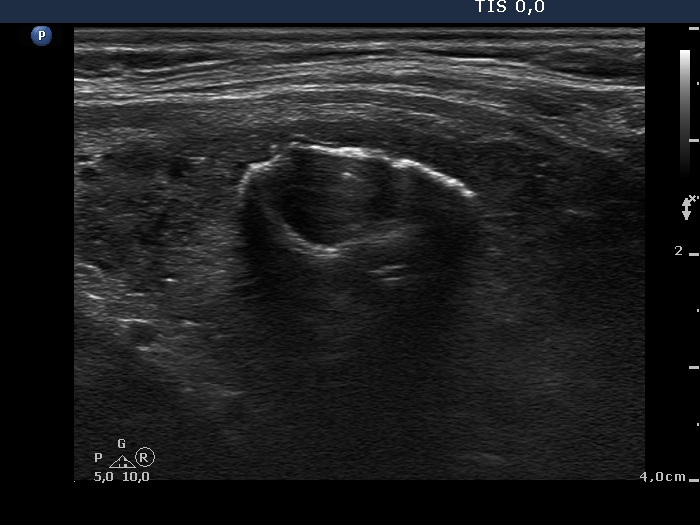

Benign hyperplastic nodule (histological diagnosis) - case cons039

|

Two foci of coarse calcification are presented, one in the left horizontal and another one in the right longitudinal scan.